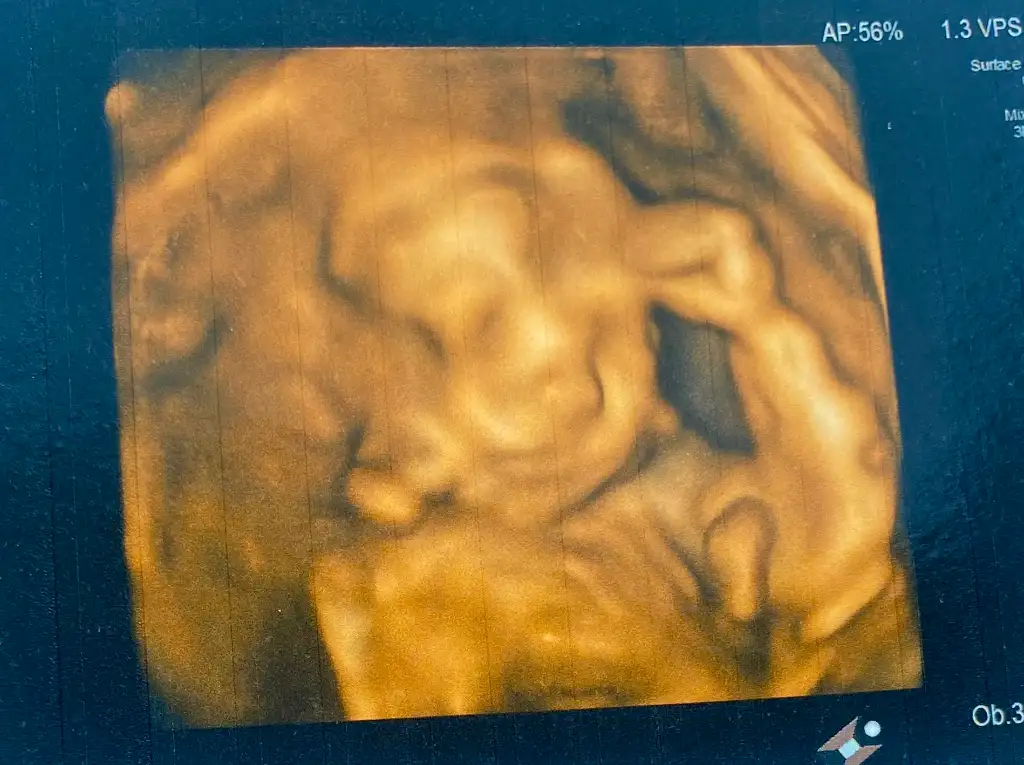

Maşallah canım benimKızlar selamlar, detaylıdan çıktık çok şükür bebeğimiz sağlıklı. Sadece bebeğime giden bir damarda daha az akış varmış kilo da olunca tabi, bol su iç dedi, sola yatma kendi doktorumda bebek aspirine başladı günde 1 tane, tansiyonumu takip edeceğiz, tuzlu yemicem. Dedim ben hareketlerini öyle net hissetmiyorum dedim kilodan dimi hocam evet dediyağ dokun seni koruduğu için daha az hissediyorsun yoksa kamerada bir hareketli. Erkek kesin ama varya çok uğraştırdı doktoru yan yattım suratını görebilmek için bebek aspirin kullanan var mıydı ? Bir de kendi doktorum bu ay içinde AKS, insülin, insülin direnci bir de HBA1C bakalım dedi. Ona göre heralde şeker yüklemesi için şey yapacak 26-27. Haftalarda yapılıyormuş o da. Ama daha istemedi isterse baktırırım bakalım.

Kilodan kaynaklı gerçekten hissedilmiyor bende kilolu hamile kaldım ilk çocuğumu 23 24 de ancak net hissetmiştim dışardan hissetmesini söylemiyorum bile birde çok ödem olmuştum onunda etkisi olmuştur belki diğerleri de aynı şekilde hissetmesi bir çok kişiye göre sonra idi yağlar hava yastığı görevi yapıyorKızlar selamlar, detaylıdan çıktık çok şükür bebeğimiz sağlıklı. Sadece bebeğime giden bir damarda daha az akış varmış kilo da olunca tabi, bol su iç dedi, sola yatma kendi doktorumda bebek aspirine başladı günde 1 tane, tansiyonumu takip edeceğiz, tuzlu yemicem. Dedim ben hareketlerini öyle net hissetmiyorum dedim kilodan dimi hocam evet dediyağ dokun seni koruduğu için daha az hissediyorsun yoksa kamerada bir hareketli. Erkek kesin ama varya çok uğraştırdı doktoru yan yattım suratını görebilmek için bebek aspirin kullanan var mıydı ? Bir de kendi doktorum bu ay içinde AKS, insülin, insülin direnci bir de HBA1C bakalım dedi. Ona göre heralde şeker yüklemesi için şey yapacak 26-27. Haftalarda yapılıyormuş o da. Ama daha istemedi isterse baktırırım bakalım.

Ayy evet bendede öyle yaptırdı, iki kolunu da koymuş kafasına çok şükür sağlıklılar ya daha ne isteriz canım Allah kucağımıza almayı nasip etsinMaşallah canım benim

Bizimki de yüzünü zor gösterdi ben de sola dönmüştüm görebilmek için